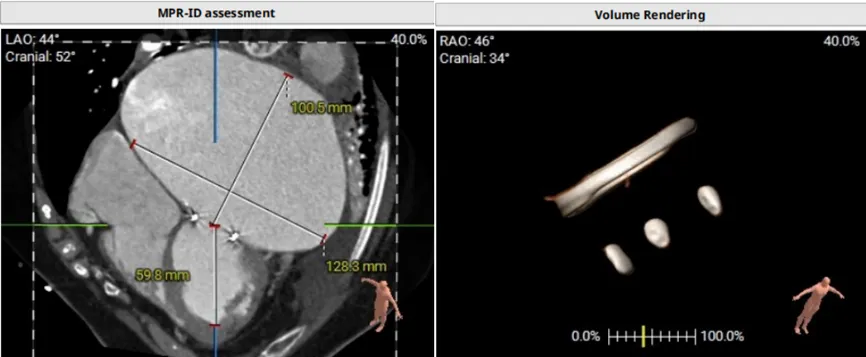

模拟植入26mm的S3瓣膜,评估LVOT阻塞风险:

1.二尖瓣环与主动脉环平面夹角= 128.3°>105°

2.瓣膜与室间隔最短距离= 6.7mm>6mm

3.最小Neo-LVOT面积= 260.4mm2>180mm2

综合评估后LVOT梗阻风险低。